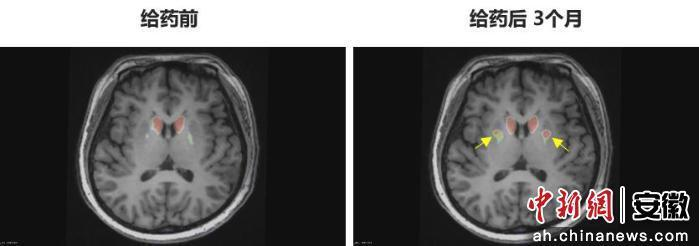

今年6月,李女士在中國科學(xué)技術(shù)大學(xué)附屬第一醫(yī)院接受了NCR201干細(xì)胞移植治療,該療法利用誘導(dǎo)多能干細(xì)胞(iPSC)衍生的多巴胺能神經(jīng)前體細(xì)胞。三個(gè)月后,她成為全球首例“功能性治愈”的帕金森病患者。

“身體不僵硬了,像正常人一樣。”李女士笑著說。多年的抖動(dòng)與“關(guān)期”徹底消失,她重新感受到身體的輕盈和心靈的自由。術(shù)后影像顯示,移植細(xì)胞已在腦內(nèi)成功定植并發(fā)揮功能,醫(yī)生稱這些“亮點(diǎn)”是新生多巴胺能神經(jīng)元的直接證據(jù)。